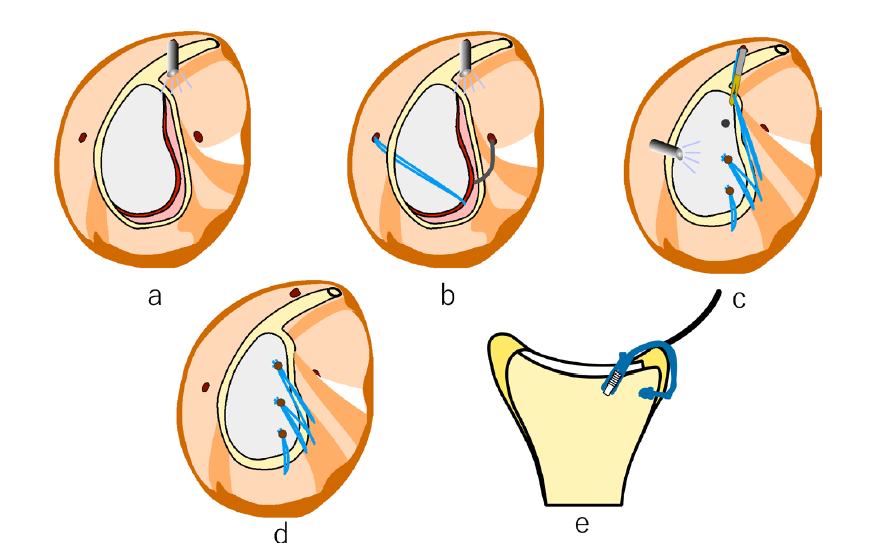

一般的な鏡視下Bankart修復術では、剥がれた関節唇を「点」で縫い合わせることが多いですが、当院が提供するDAFF(Double Anchor Footprint Fixation)法は、靭帯を関節窩(肩の受け皿)の「面」に固定します。

- 面での強固な固定: 前下肩甲上腕靭帯(AIGHL)を広い範囲で骨に密着させることで、より生理的な修復と強固な安定性を実現します。

- 最新デバイスの活用: Smith & Nephew社の「マイクロラプターノットレス」などの最新アンカーをいち早く導入。挿入時のトラブルを回避し、1mm単位の精度を保ちながら手術時間を短縮します。